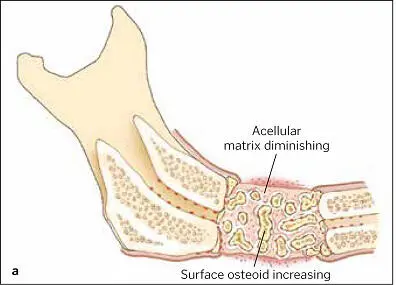

FIG 1-16 (a and b) At about 6 weeks, the graft begins a major resorption-remodeling cycle in which osteoclasts resorb the disorganized immature bone and release BMP and insulinlike growth factors, thus inducing formation of new bone that will mature during function. (Reprinted with permission from Marx and Garg. 1)